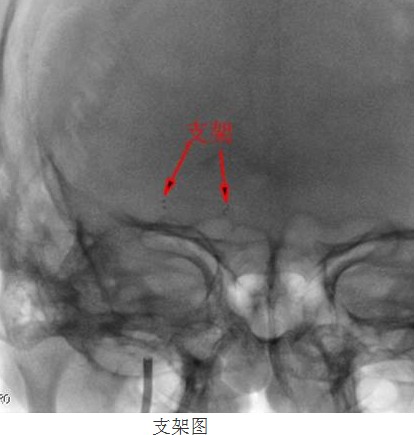

113號(hào)患者被送進(jìn)了DSA室內(nèi),在南方醫(yī)科大學(xué)劉亞杰教授的指導(dǎo)下,患者在靜脈全麻下(在麻醉科龍宏杰主任積極配合下),行“右側(cè)大腦中動(dòng)脈血管成形及支架植入術(shù)”。

常規(guī)準(zhǔn)備后,神經(jīng)內(nèi)科顏津津主治醫(yī)師在助手高彬醫(yī)師配合下采用Seldinger法穿刺股動(dòng)脈,置導(dǎo)管鞘、引導(dǎo)管,在導(dǎo)絲帶引下將導(dǎo)引導(dǎo)管放置右側(cè)頸內(nèi)動(dòng)脈巖部造影,后在透視下,順著造影路圖,小心將微導(dǎo)絲、微導(dǎo)管通過(guò)狹窄處并置入右側(cè)大腦中動(dòng)脈M3段,接著撤出微導(dǎo)管,順著微導(dǎo)絲置入Gateway球囊, 至狹窄部位,經(jīng)造影骨性標(biāo)志等多重定位后證實(shí)球囊位置良好,接壓力泵緩慢加壓擴(kuò)張,撤出球囊造影,顯示血管成形良好。選取Wingspan支架, 順微導(dǎo)絲將支架輸送器小心送至狹窄處,造影定位確認(rèn)支架位置準(zhǔn)確覆蓋狹窄部位,釋放支架,撤出支架輸送器,造影證實(shí)血管狹窄處成形良好,觀察10分鐘后再次造影,支架無(wú)移位,狹窄處遠(yuǎn)端血管完整,未見血管狹窄、造影劑外滲。撤除導(dǎo)絲、導(dǎo)引導(dǎo)管,患者術(shù)后24小時(shí)可下床自行活動(dòng),術(shù)后1周順利出院,生活基本恢復(fù)正常,并叮囑梁伯繼續(xù)堅(jiān)持服藥,定期復(fù)診。

“大腦中動(dòng)脈血管成形及支架植入術(shù)”為我院首例顱內(nèi)支架植入手術(shù),其順利完成,標(biāo)志著我院在神經(jīng)介入診療方面的水平又上了一個(gè)新的臺(tái)階!